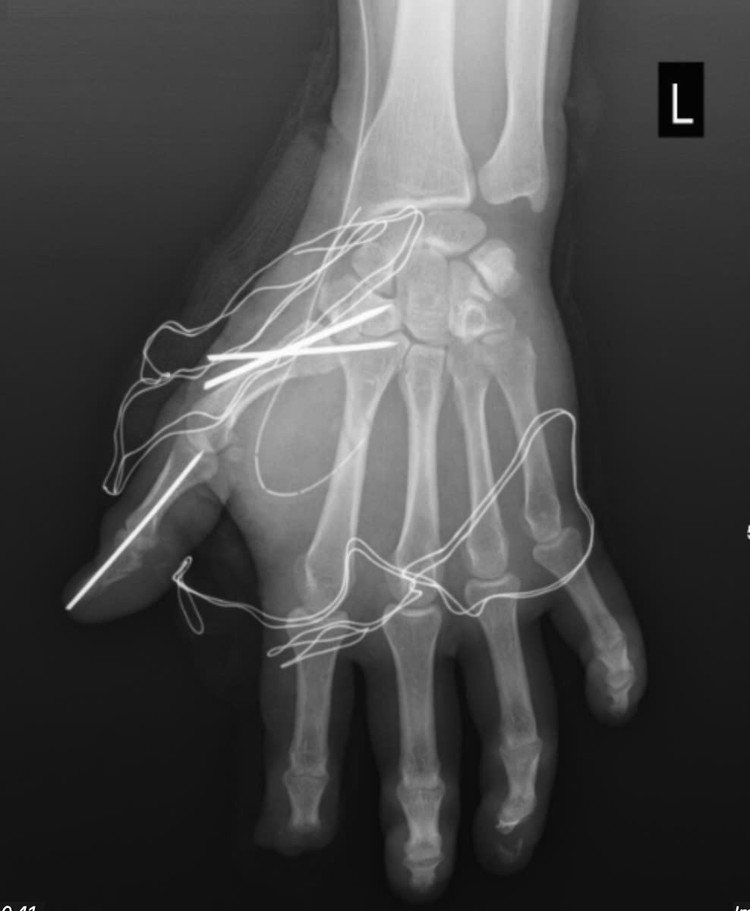

Trong quá trình phẫu thuật, các bác sĩ Khoa Phẫu thuật chấn thương chỉnh hình và y học thể thao đã tiến hành cắt lọc tổ chức dập nát, lấy bỏ dị vật trên bàn tay của người bệnh. Đồng thời, các bác sĩ làm sạch vết thương, bảo tồn tối đa cấu trúc gân, thần kinh và mạch máu còn lại cho người bệnh. Cuối cùng, các bác sĩ đã cố định xương gãy và khớp bị trật cho người bệnh.

tai-nan-phao-no.jpg

Tổn thương sau phẫu thuật - Ảnh BVCC